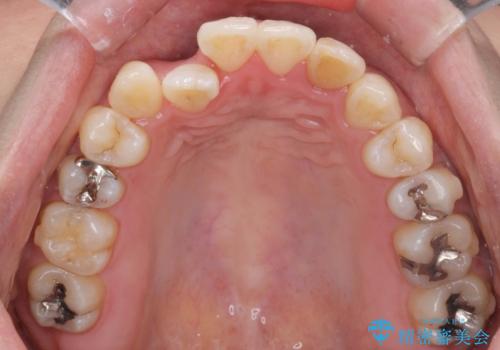

引っ込んだ前歯を並べたい マウスピースと部分ワイヤーのコンビネーション矯正

- 引っ込んで生えてしまっている前歯を並べたい、と矯正治療を希望され来院されました。

まずマウスピース矯正インビザラインシステムで、引っ込んだ歯が並ぶためのスペースを作ったのち、部分ワイヤー矯正を行い短期間での配列を計画します。

マウスピース・ワイヤーそれぞれの長所をうまく活かすことで治療期間の短縮が可能となります。

このように前歯の部分ワイヤーは引っ込んでしまった前歯や がたつきを素早く改善することができます。